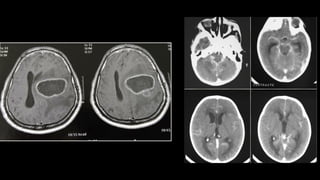

3) Condições que comprometem encéfalo globalmente

Algumas causas muito raras:

- Infartos talâmicos bilaterais

- Hematomas Subdurais bilaterais

- Hemorragia subaracnóidea

- Meningite / Encefalite Infarto talâmico Bilateral – Artéria de Pecheron

CAUSA: I - Estrutural Supratentorial

• Trauma:

– lesão axonal difusa

– Sangramentos intracranianos:

. Hematomas subdurais ou extradurais

. HIP

• Vascular:

– AVCs 🡪 hemorragias/ isquemia cerebral extensa / vasoespasmo

por HSA aneurismática

– Isquemia talâmica bilateral

– Trombose de seio cerebral